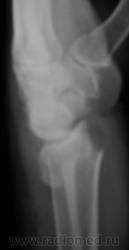

Случай 4.

Случай 5.